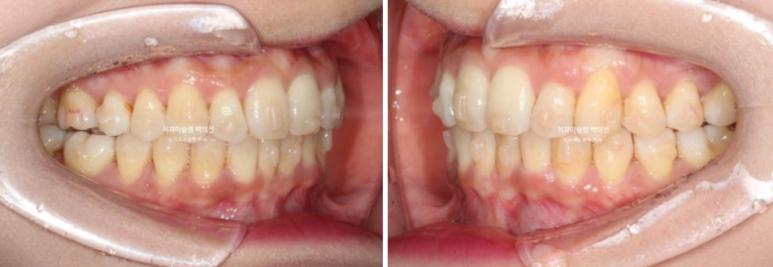

송곳니와 작은어금니 덧니가 보이며 작은어금니가 거꾸로 물리는 반대교합도 보입니다.

앞니 중심선은 약 2mm 어긋나 있습니다.

위 앞니가 아래앞니를 많이 덮어 깊게 물리는 과개교합도 있습니다.

덧니쪽으로 중심선이 돌아가 있네요. 중심선이 돌아가 있으면 뼈의 비대칭이 비대칭처럼 보입니다.

이전 다른병원에서 교정상담을 받으면서 앞니가 옥니라는 진단도 받고 오셨죠.

옥니, 덧니, 과개교합, 반대교합, 중심선 불일치를 인비절라인으로 고치기로 합니다.